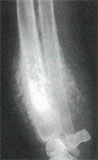

・レントゲン検査

麻痺などの神経異常を疑う場合には神経学的検査、骨の異常を疑う場合にはレントゲン検査、

・骨折